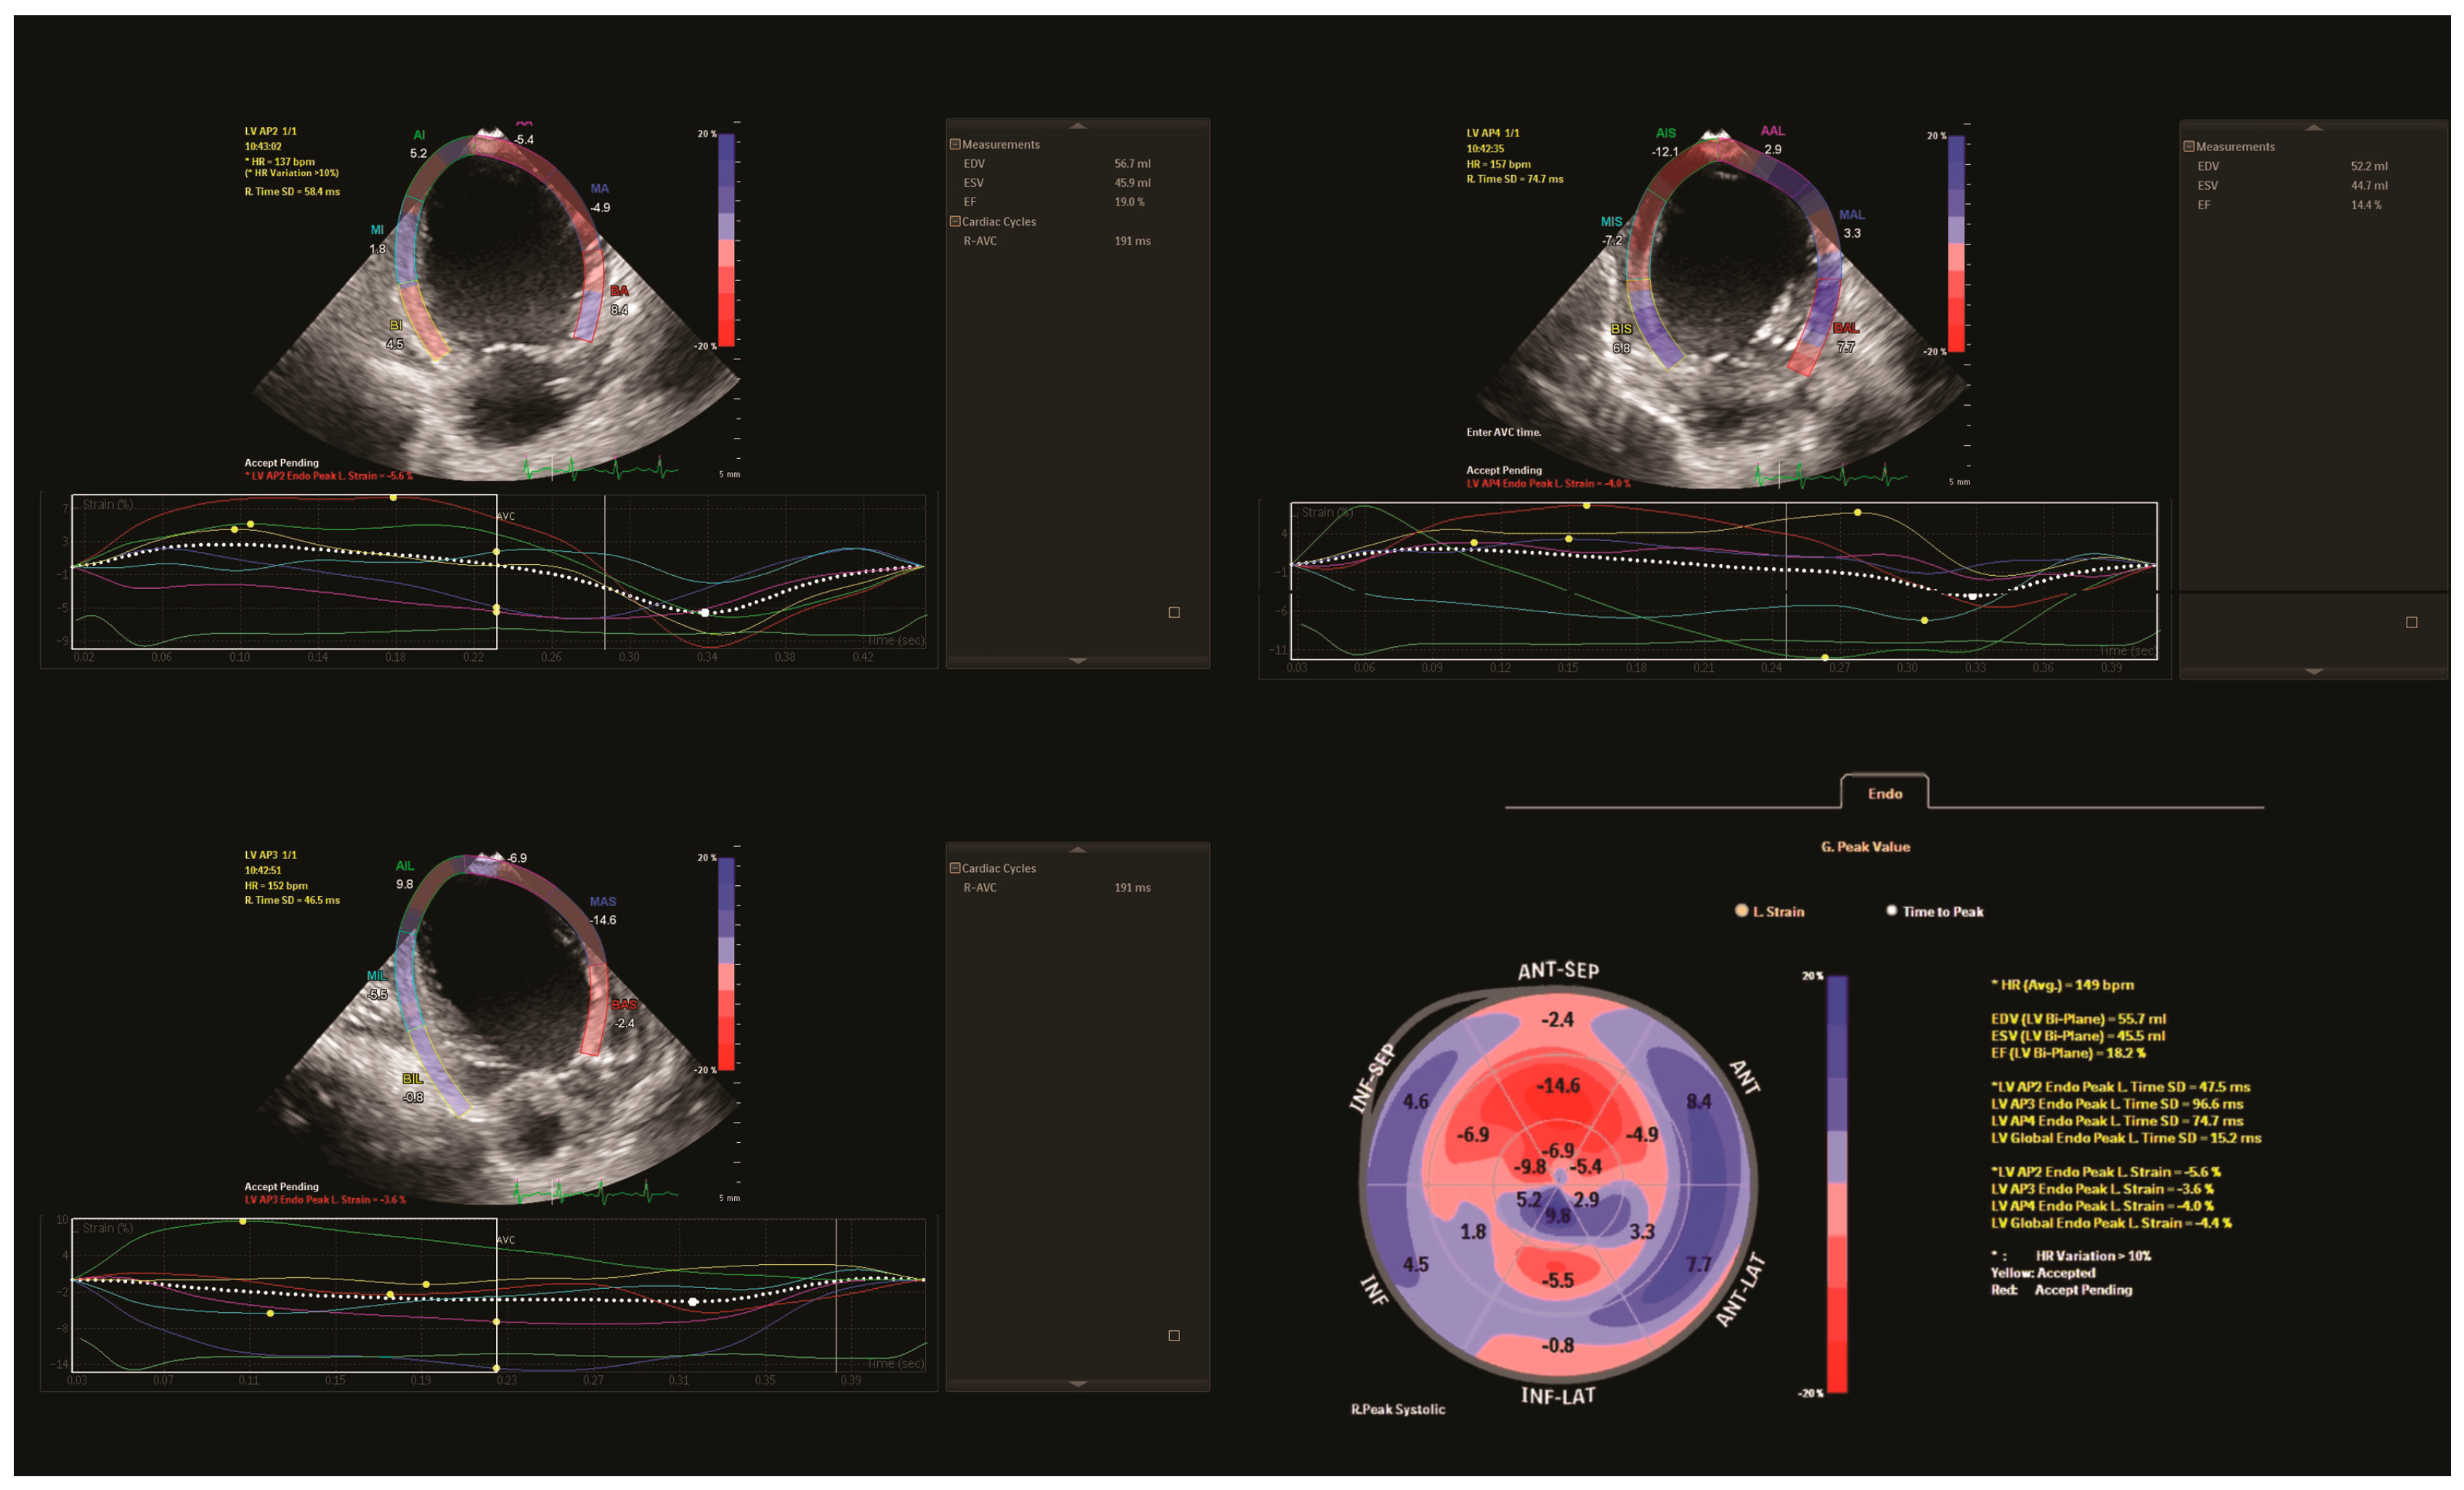

Using the Simpson method, LV EF was calculated using conventional echocardiography (18.3%). The speckle-tracking analysis assessed the regional myocardial function of individual segments and global longitudinal strain (GLS). Longitudinal strain measurements of the LV were low in all views (two-chamber: −5.6%, three-chamber: −3.6% and four-chamber: −4.6%), with impaired GLS (−4.4%). The analysis revealed hypokinetic anterior, anterolateral, and inferior LV regions with a hypokinetic septum, corresponding to territories supplied by both the LCA and the right coronary artery (RCA) (Figure 2).

Figure 2.

Preoperative speckle-tracking analysis. LV longitudinal strain from the apical two, three and four-chamber view. Time-strain curves show a pathological deformation in the anterior, anterolateral, and inferior LV regions with a hypokinetic septum. Final bull’s-eye plot reveals low global longitudinal strain with severe impairment of both left and right coronary artery territories that supply the left ventricle. AP2: apical two-chamber view; AP3: apical three-chamber view; AP4: apical four-chamber view; EDV (bi-plane): end-diastolic volume (bi-plane); ESV (bi-plane): end-systolic volume (bi-plane); EF (bi-plane): ejection fraction (bi-plane); Global Endo Peak L. Strain (GLS): global longitudinal strain; and HR: heart rate.